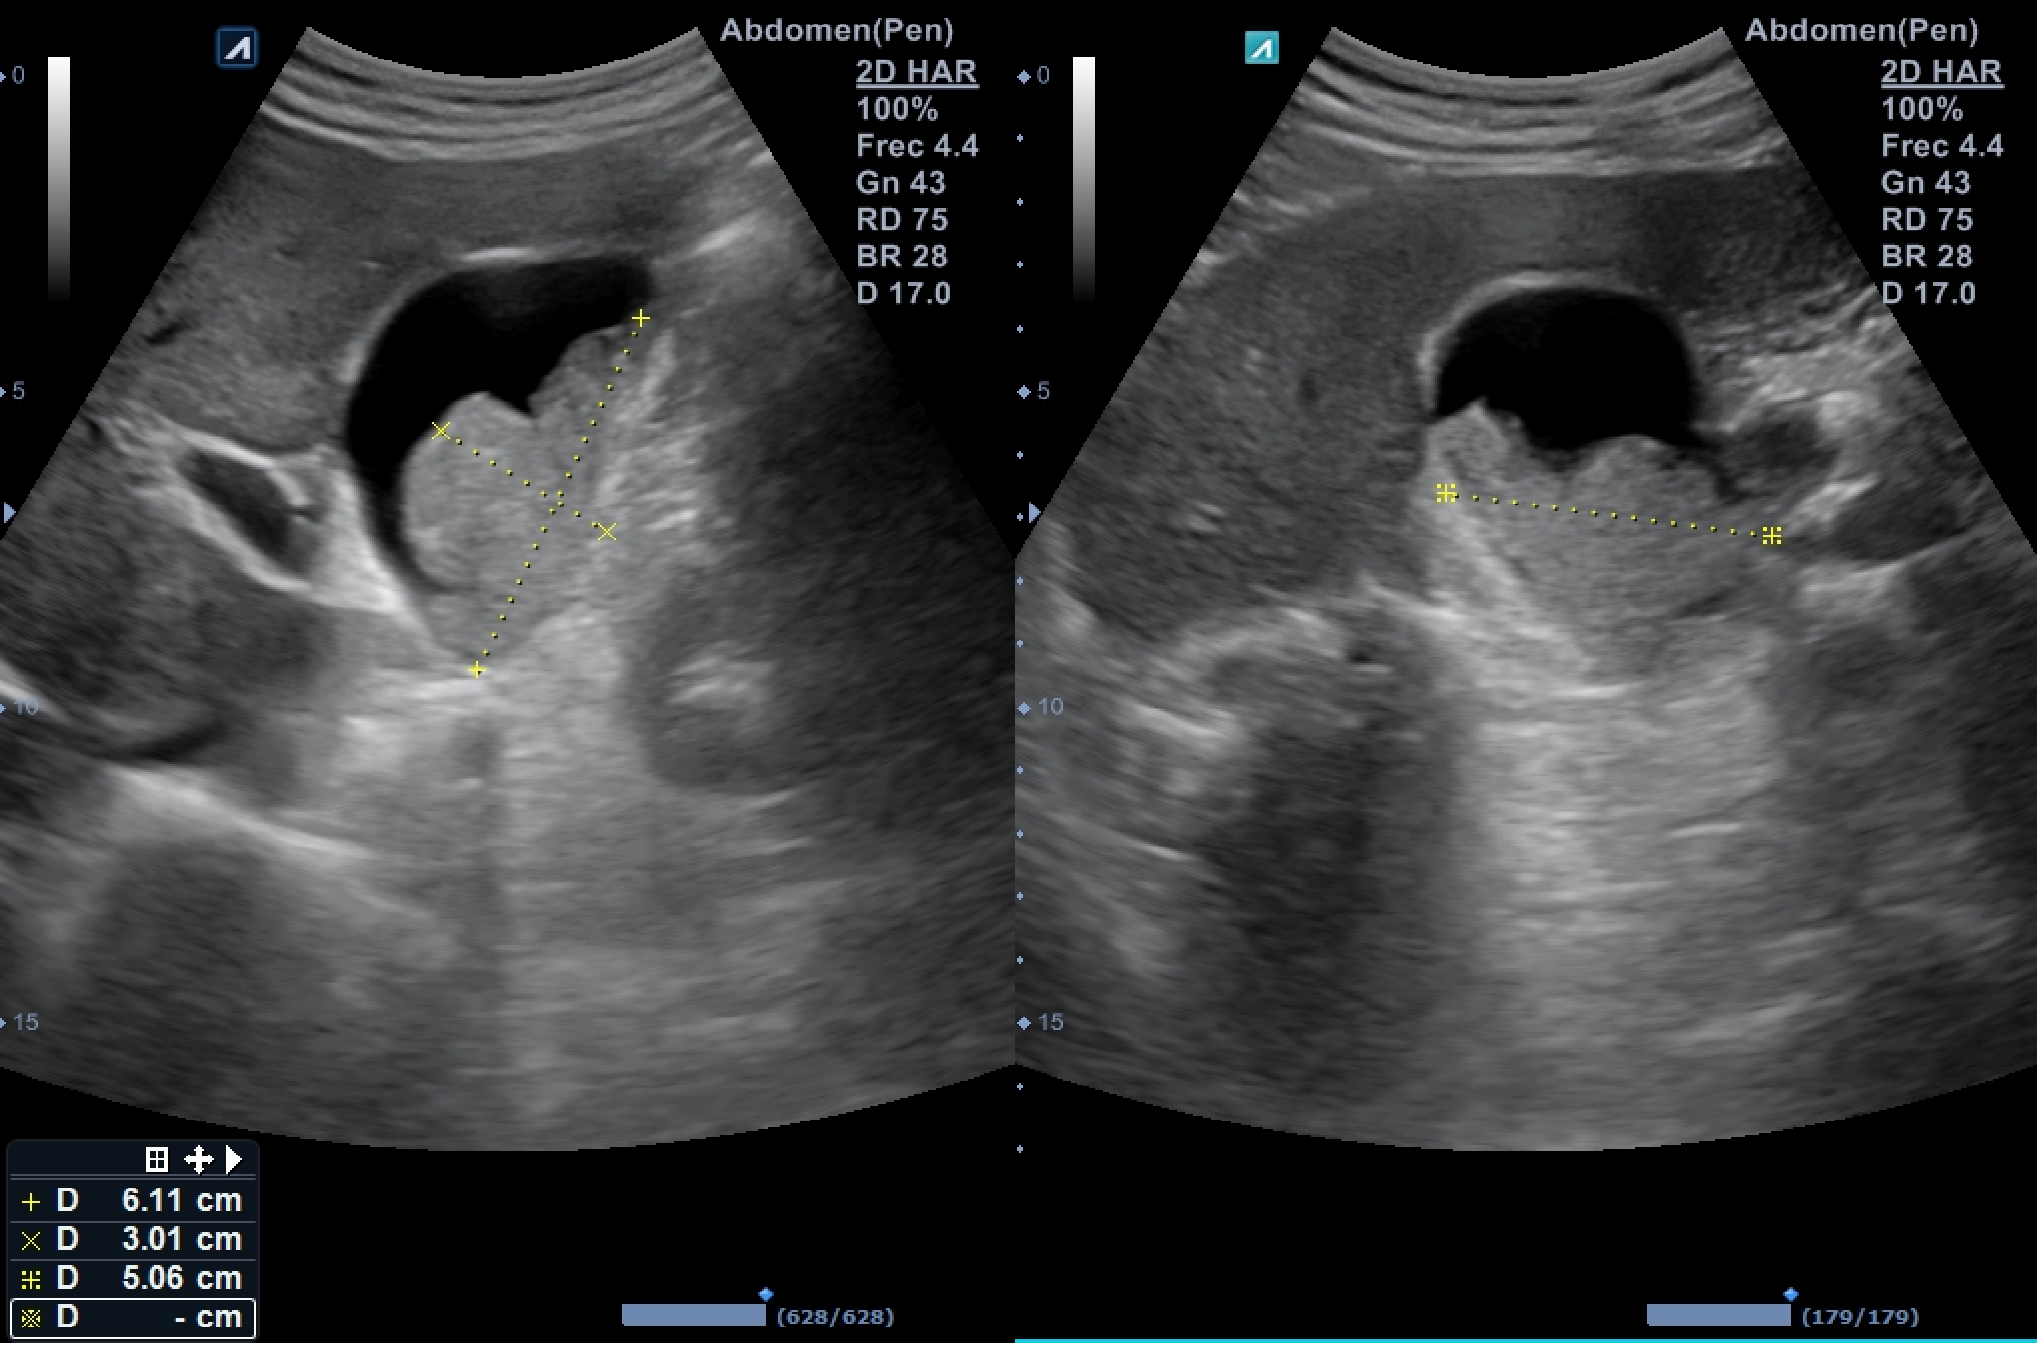

Ecografía abdominal dónde destaca vesícula biliar de pared fina (hasta 3,4 milímetros en su punto de mayor grosor) sin colecciones perivesiculares, que alberga en su interior imagen polilobulada sólida de efecto masa dependiente de su pared posterolateral e inferior que ocupa más de la mitad de la luz, sin captación de flujo Doppler, sugerente de polipoidea o tumoral, de unos 6 x 5 x 3 centímetros de dimensiones mayores.